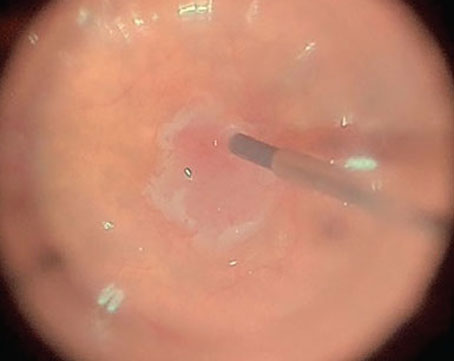

Surgical tips for single 27-gauge vitrectomy for navigating through tight surgical planes in tractional retinal detachments.